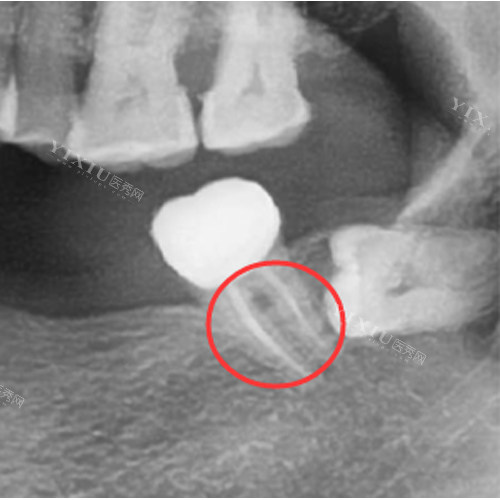

根管治疗是一种治疗牙髓病和根尖周病的有效方法,它通过清除根管内的炎症牙髓和坏死物质,并进行适当消毒,充填根管,以去除根管内容物对根尖周围组织的不良刺激,防止发生根尖周病变或促进根尖周病变的愈合。但根管治疗确实存在失败感染的可能性。

根管解剖结构复杂:人类牙齿的根管系统非常复杂,存在许多变异情况。例如,根管可能存在侧支根管、副根管等,这些细小的分支在治疗过程中很难被完全清理和充填。

细菌可能会残留在这些未被处理到的部位,随着时间的推移,就可能导致感染复发,从而使根管治疗失败。